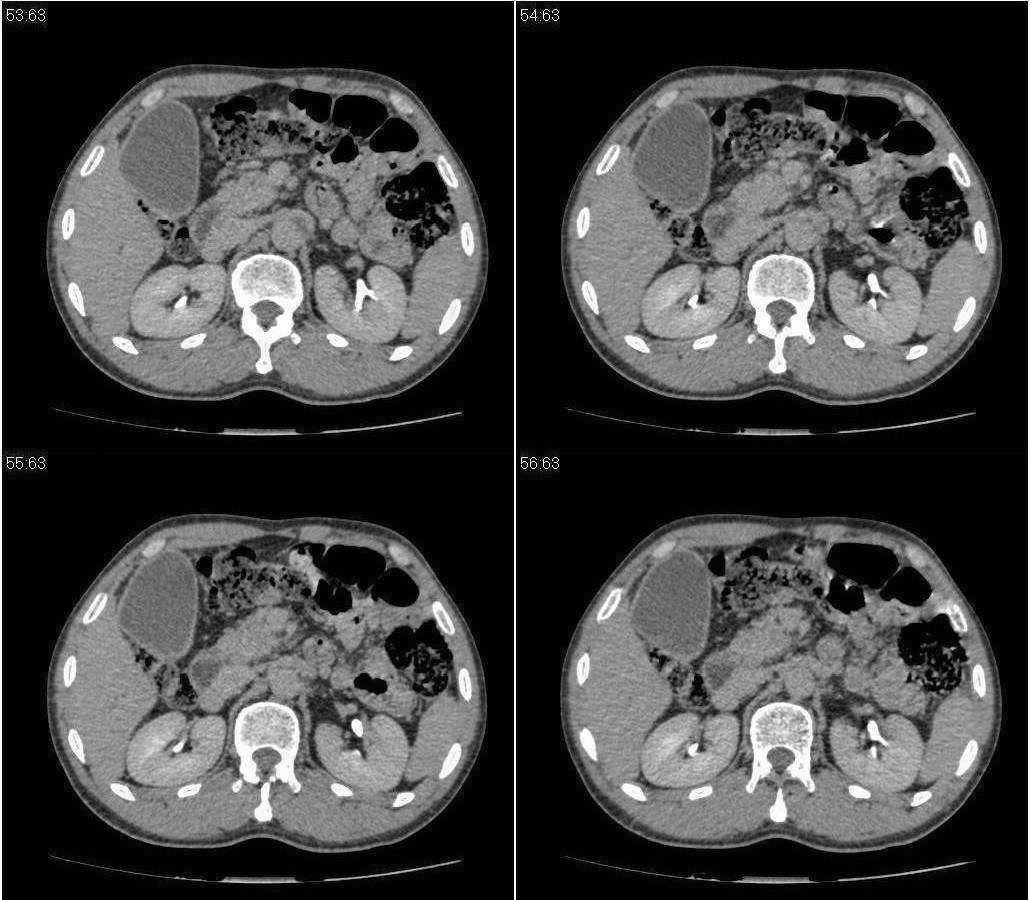

标题: CT21384:男性,50岁。发现无痛性黄疸十余天,B朝提示肝胆管 [打印本页]

标题: CT21384:男性,50岁。发现无痛性黄疸十余天,B朝提示肝胆管

1.考虑:壶腹占位病变(癌?)。

2.胆系低位梗阻:肝内外胆管扩张,胆囊增大,胰管扩张。

胆系低位梗阻(肝内外胆管扩张,胆囊增大,胰管扩张);考虑胰头癌或壶腹癌所致。

考虑胰头段胆管占位

胰头强化欠均匀,胆胰管扩张。考虑胰头癌可能性大。

胆系低位梗阻(肝内外胆管扩张,胆囊增大,胰管扩张,钩突似有占位);考虑胰头癌